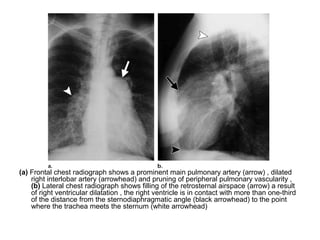

(a) Frontal chest radiograph shows a prominent main pulmonary artery (arrow) , dilated

right interlobar artery (arrowhead) and pruning of peripheral pulmonary vascularity ,

(b) Lateral chest radiograph shows filling of the retrosternal airspace (arrow) a result

of right ventricular dilatation , the right ventricle is in contact with more than one-third

of the distance from the sternodiaphragmatic angle (black arrowhead) to the point

where the trachea meets the sternum (white arrowhead)